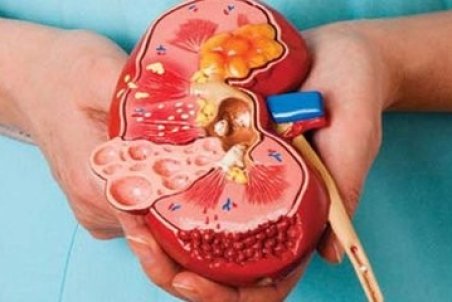

یک فوق تخصص بیماریهای کلیه عوامل خطر ایجاد سنگ کلیه در افراد، بدون علامت بودن سنگها، وجود دردهای شدید در کلیه، راههای پیشگیری و توصیههای تغذیهای برای جلوگیری از بروز از سنگ سازیهای بعدی در کلیه را تشریح کرد.

معمولاً سنگهای کلیه کوچک، بدون بروز علائم و مشکلات خاصی دفع میشوند اما سنگهای بزرگتر در مجاری ادراری لانه میکنند و منجر به درد میشوند؛ اگر این سنگها دفع نشوند، میتوانند عوارضی چون عفونت یا آسیبهای کلیوی را بهدنبال داشته باشند.